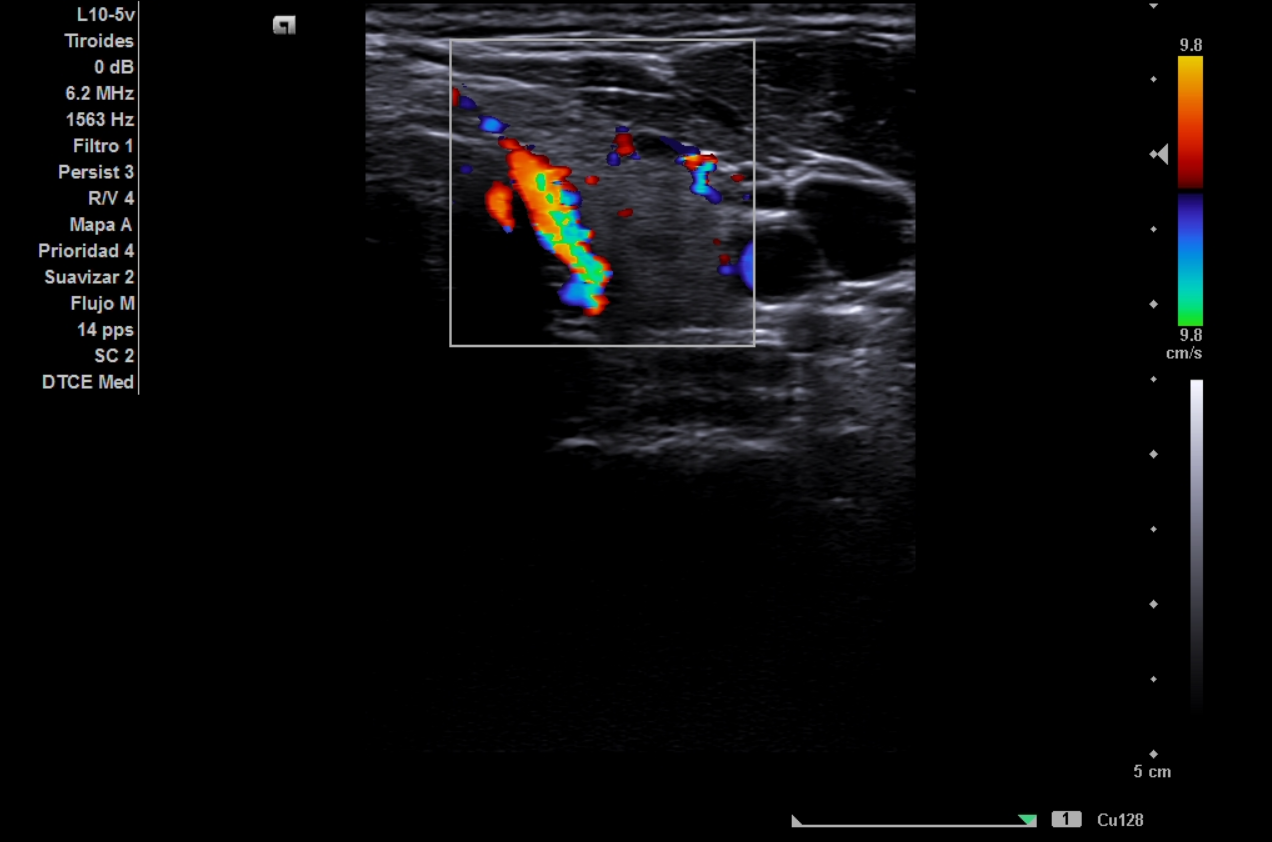

La ecografía clínica de tiroides muestra lóbulo derecho de 18 mm y lóbulo izquierdo de 16,7 mm en eje anteroposterior, con ecoestructura hipoecoica y heterogénea, presencia de múltiples quistes anecoicos milimétricos y un discreto aumento de la vascularización. No se identifican nódulos sólidos. El Doppler registra un pico sistólico máximo de 23 cm/s en ambas arterias tiroideas inferiores. Estos hallazgos son compatibles con tiroiditis.

Ecográficamente, la enfermedad de Graves se caracteriza por hipervascularización difusa («inferno tiroideo») y velocidades sistólicas elevadas (>30 cm/s), mientras que en las tiroiditis la vascularización es normal o discretamente aumentada, con patrón heterogéneo sin hiperflujo marcado.